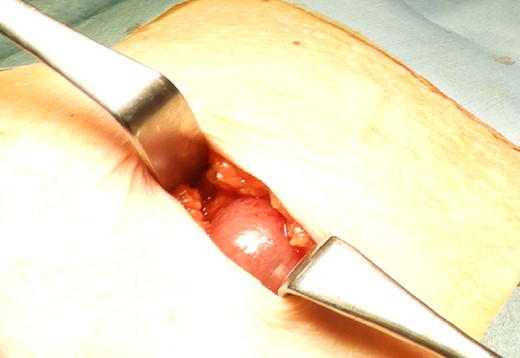

The drain was removed on postoperative day 2. On the night of the third postoperative day, the patient vomited. On the morning of the fourth postoperative day, mild abdominal pain and a ping-pong ball-sized bulge and induration were found near the surgical scar of the 5 mm port where the drain had been placed. CT confirmed an incarcerated small intestine and ileus in the 5 mm port scar where the drain had been placed (Fig. 2). Ileus removal was performed on the same day. First, the dilated wound for nephrectomy was opened, and the inside of the abdominal cavity was observed. A hanging small intestine was observed just below the 5 mm port (Fig. 3). Since it could not be conquered manually, a 2 cm vertical incision was made on the 5 mm port wound. The small intestine penetrated the anterior layer of the rectus abdominis muscle, so the fascia was carefully incised to avoid damaging the small intestine. The small intestine was returned to the abdominal cavity. The small intestine was slightly discolored (Fig. 4), but after discussion with the gastrointestinal surgeon, it was determined that it was not necrotic. No small intestine resection was performed. The wound was carefully closed using fascial sutures to prevent recurrence. The fascia was weak, likely because this patient was taking steroids. The ileus has not recurred since then. The pathological results indicated a maximum diameter of 30 mm, consistent with papillary renal cell carcinoma, classified as pT1a G3 > G2, with negative margins.

CT showing small intestine penetrating fascia of rectus abdominis. The arrow shows the incarcerated small intestine.